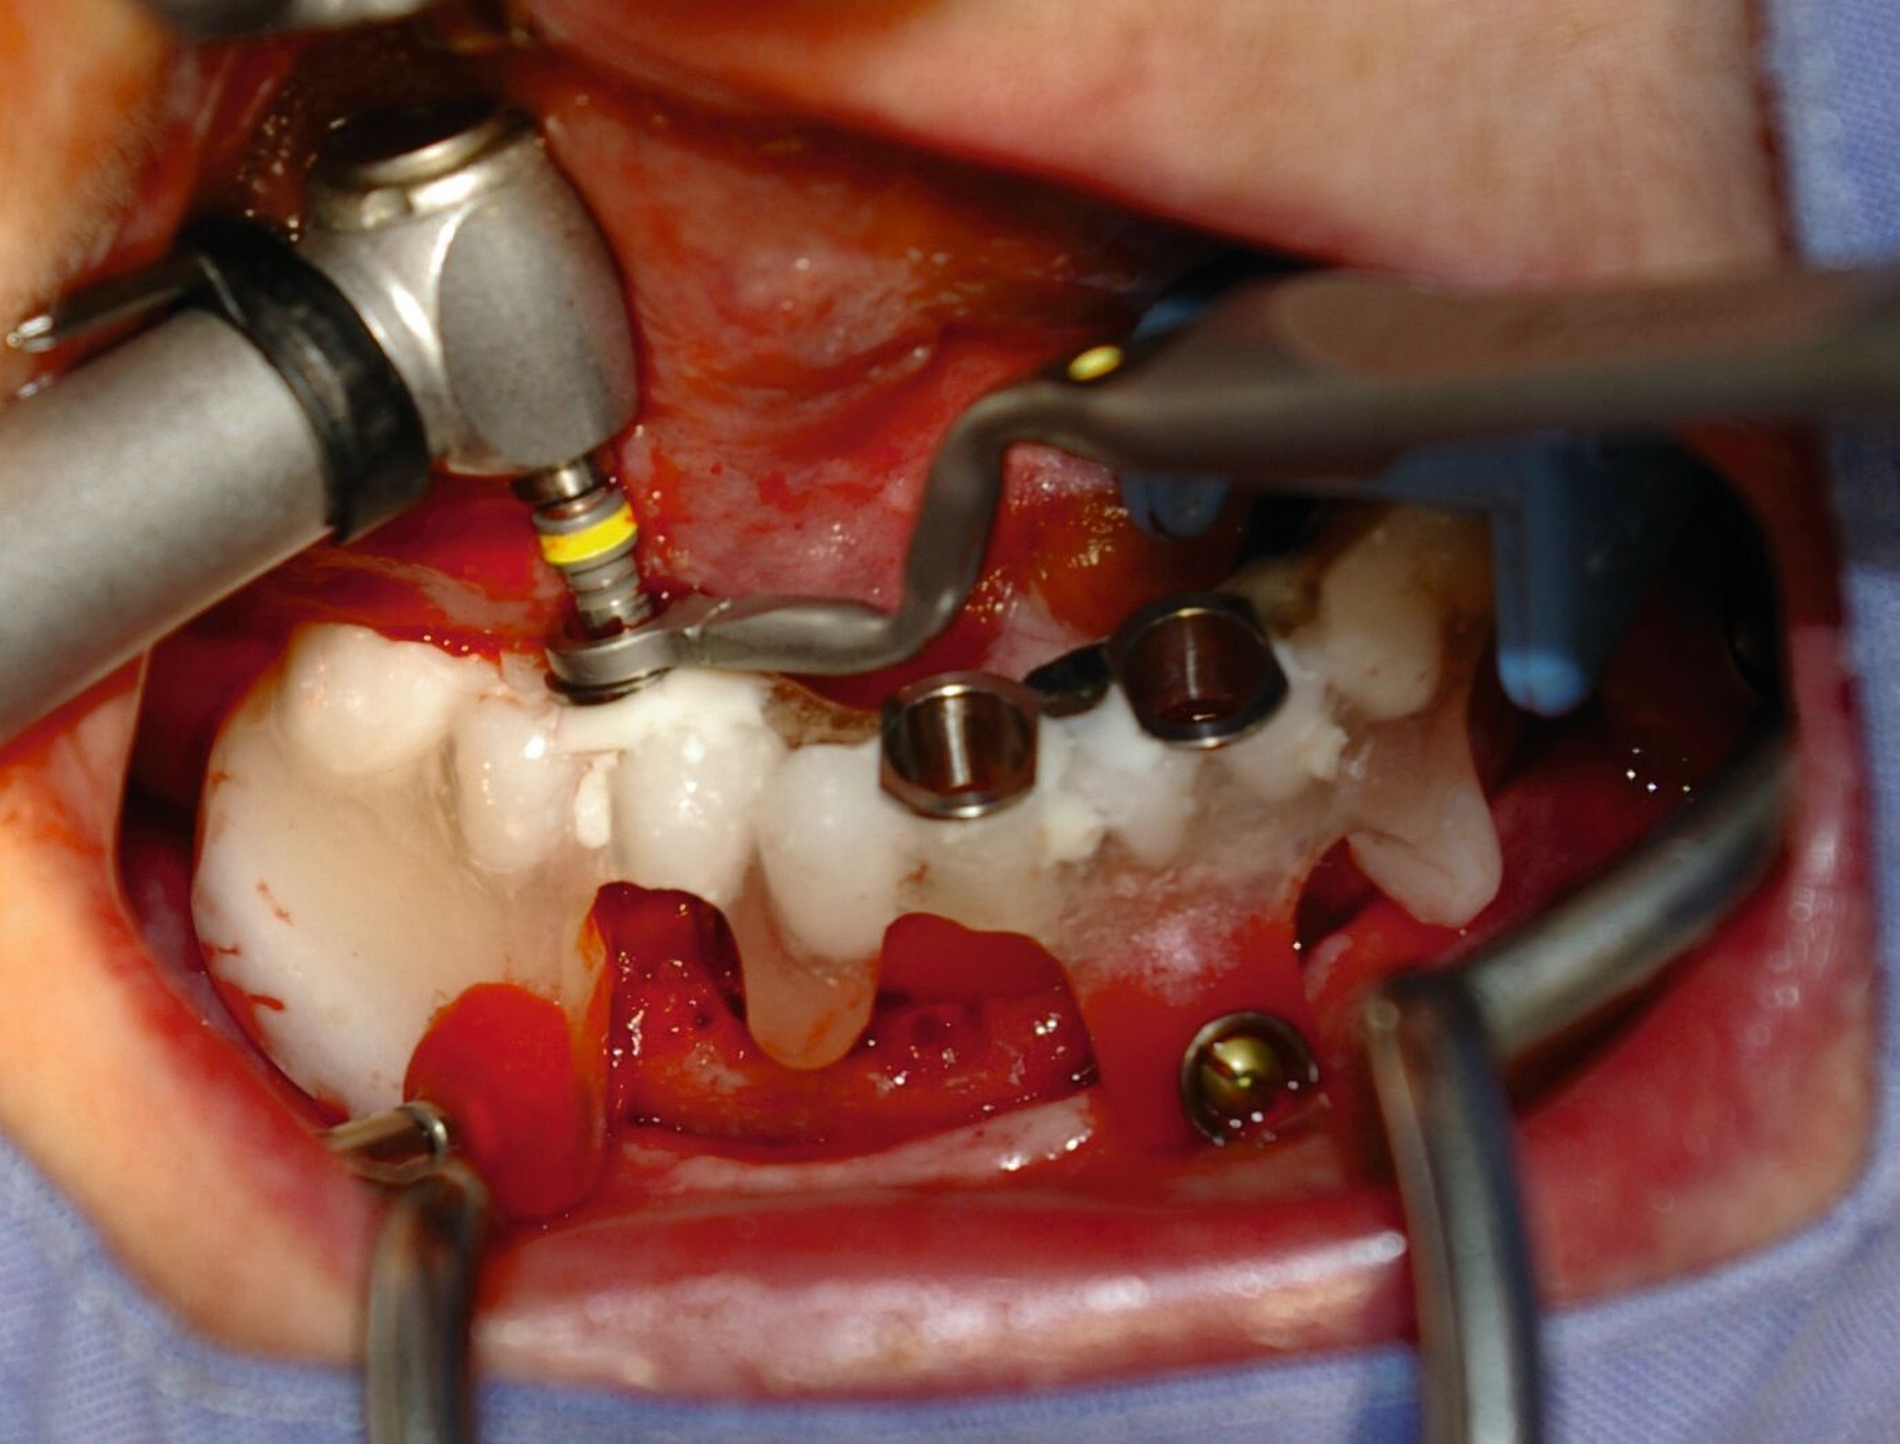

Nach Abheilung und erneutem DVT werden in intravenöser Analogsedation (Operator Side) vier interforaminäre Implantate (Straumann Tissue Level, Straumann, Basel) geplant und geführt inseriert (Labor Rübeling und Klar, Organical Planner, ZTM Daniel Ellmann, Berlin).